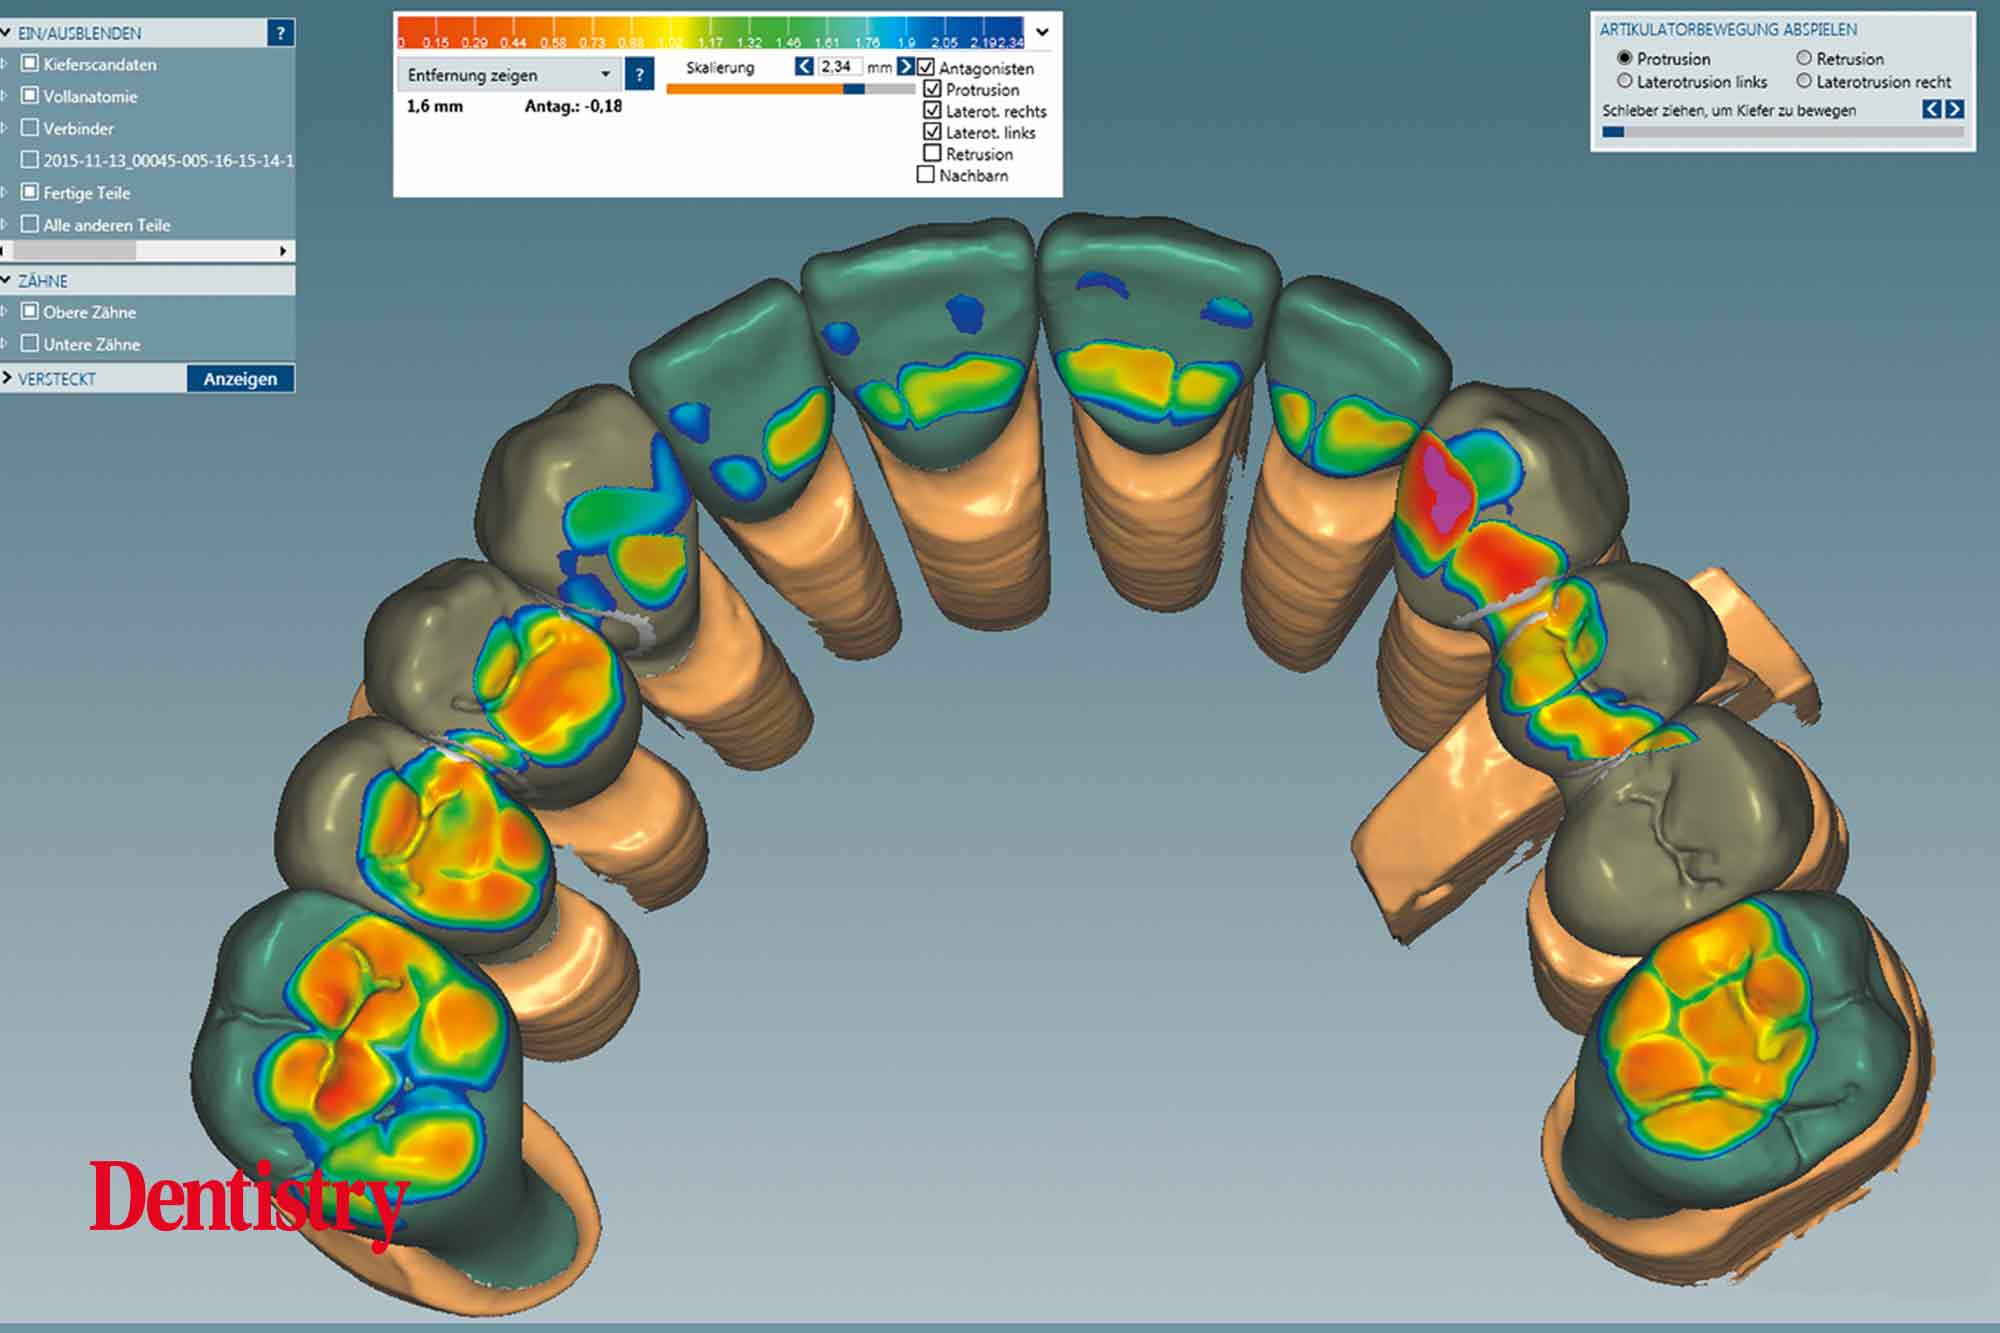

The scanned models were evaluated on a virtual 11 articulator. Temporary Ceramill PMMA (Amann Girrbach) transparent acrylic crowns were CAD planned (Figures 3a to 3d).

Patient data including condylar movements were recorded by the software. Using the Initial situation software’s customised incisal guide unit, the incisal guide pin was adjusted on the splitex plate to the desired cuspal inclinations on the virtual temporary crowns (Figure 4).

All patient parameters including condylar inclination were transferred to the Ceramill Artex articulator and the lateral and protrusive excursions were established while having no contact with the anterior teeth (Figures 5 to 8).